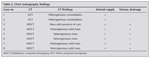

The chest CT findings as shown on Table 1 were solid mass lesion (5 patients), heterogeneous consolidation (2 patients), and cystic lesion with aberrant systemic arterial supply (8 cases): venous return could be demonstrated in 6 cases. In two cases examined with helical CT the venous return could not be demonstrated. The feeding artery was mostly from the descending thoracic aorta (n= 6). Feeding arteries were arising from arcus aorta (n= 1), internal mammary artery (n= 1), intercostals (n= 2) and celiac axis (n= 1). Four patients underwent surgery. One patient underwent angiography with embolization using N-butyl cyanoacrilate particle. The patient characteristics, clinical symptoms, chest radiograph and angiographic findings, and the treatment offered are briefly summarized in Table 2.